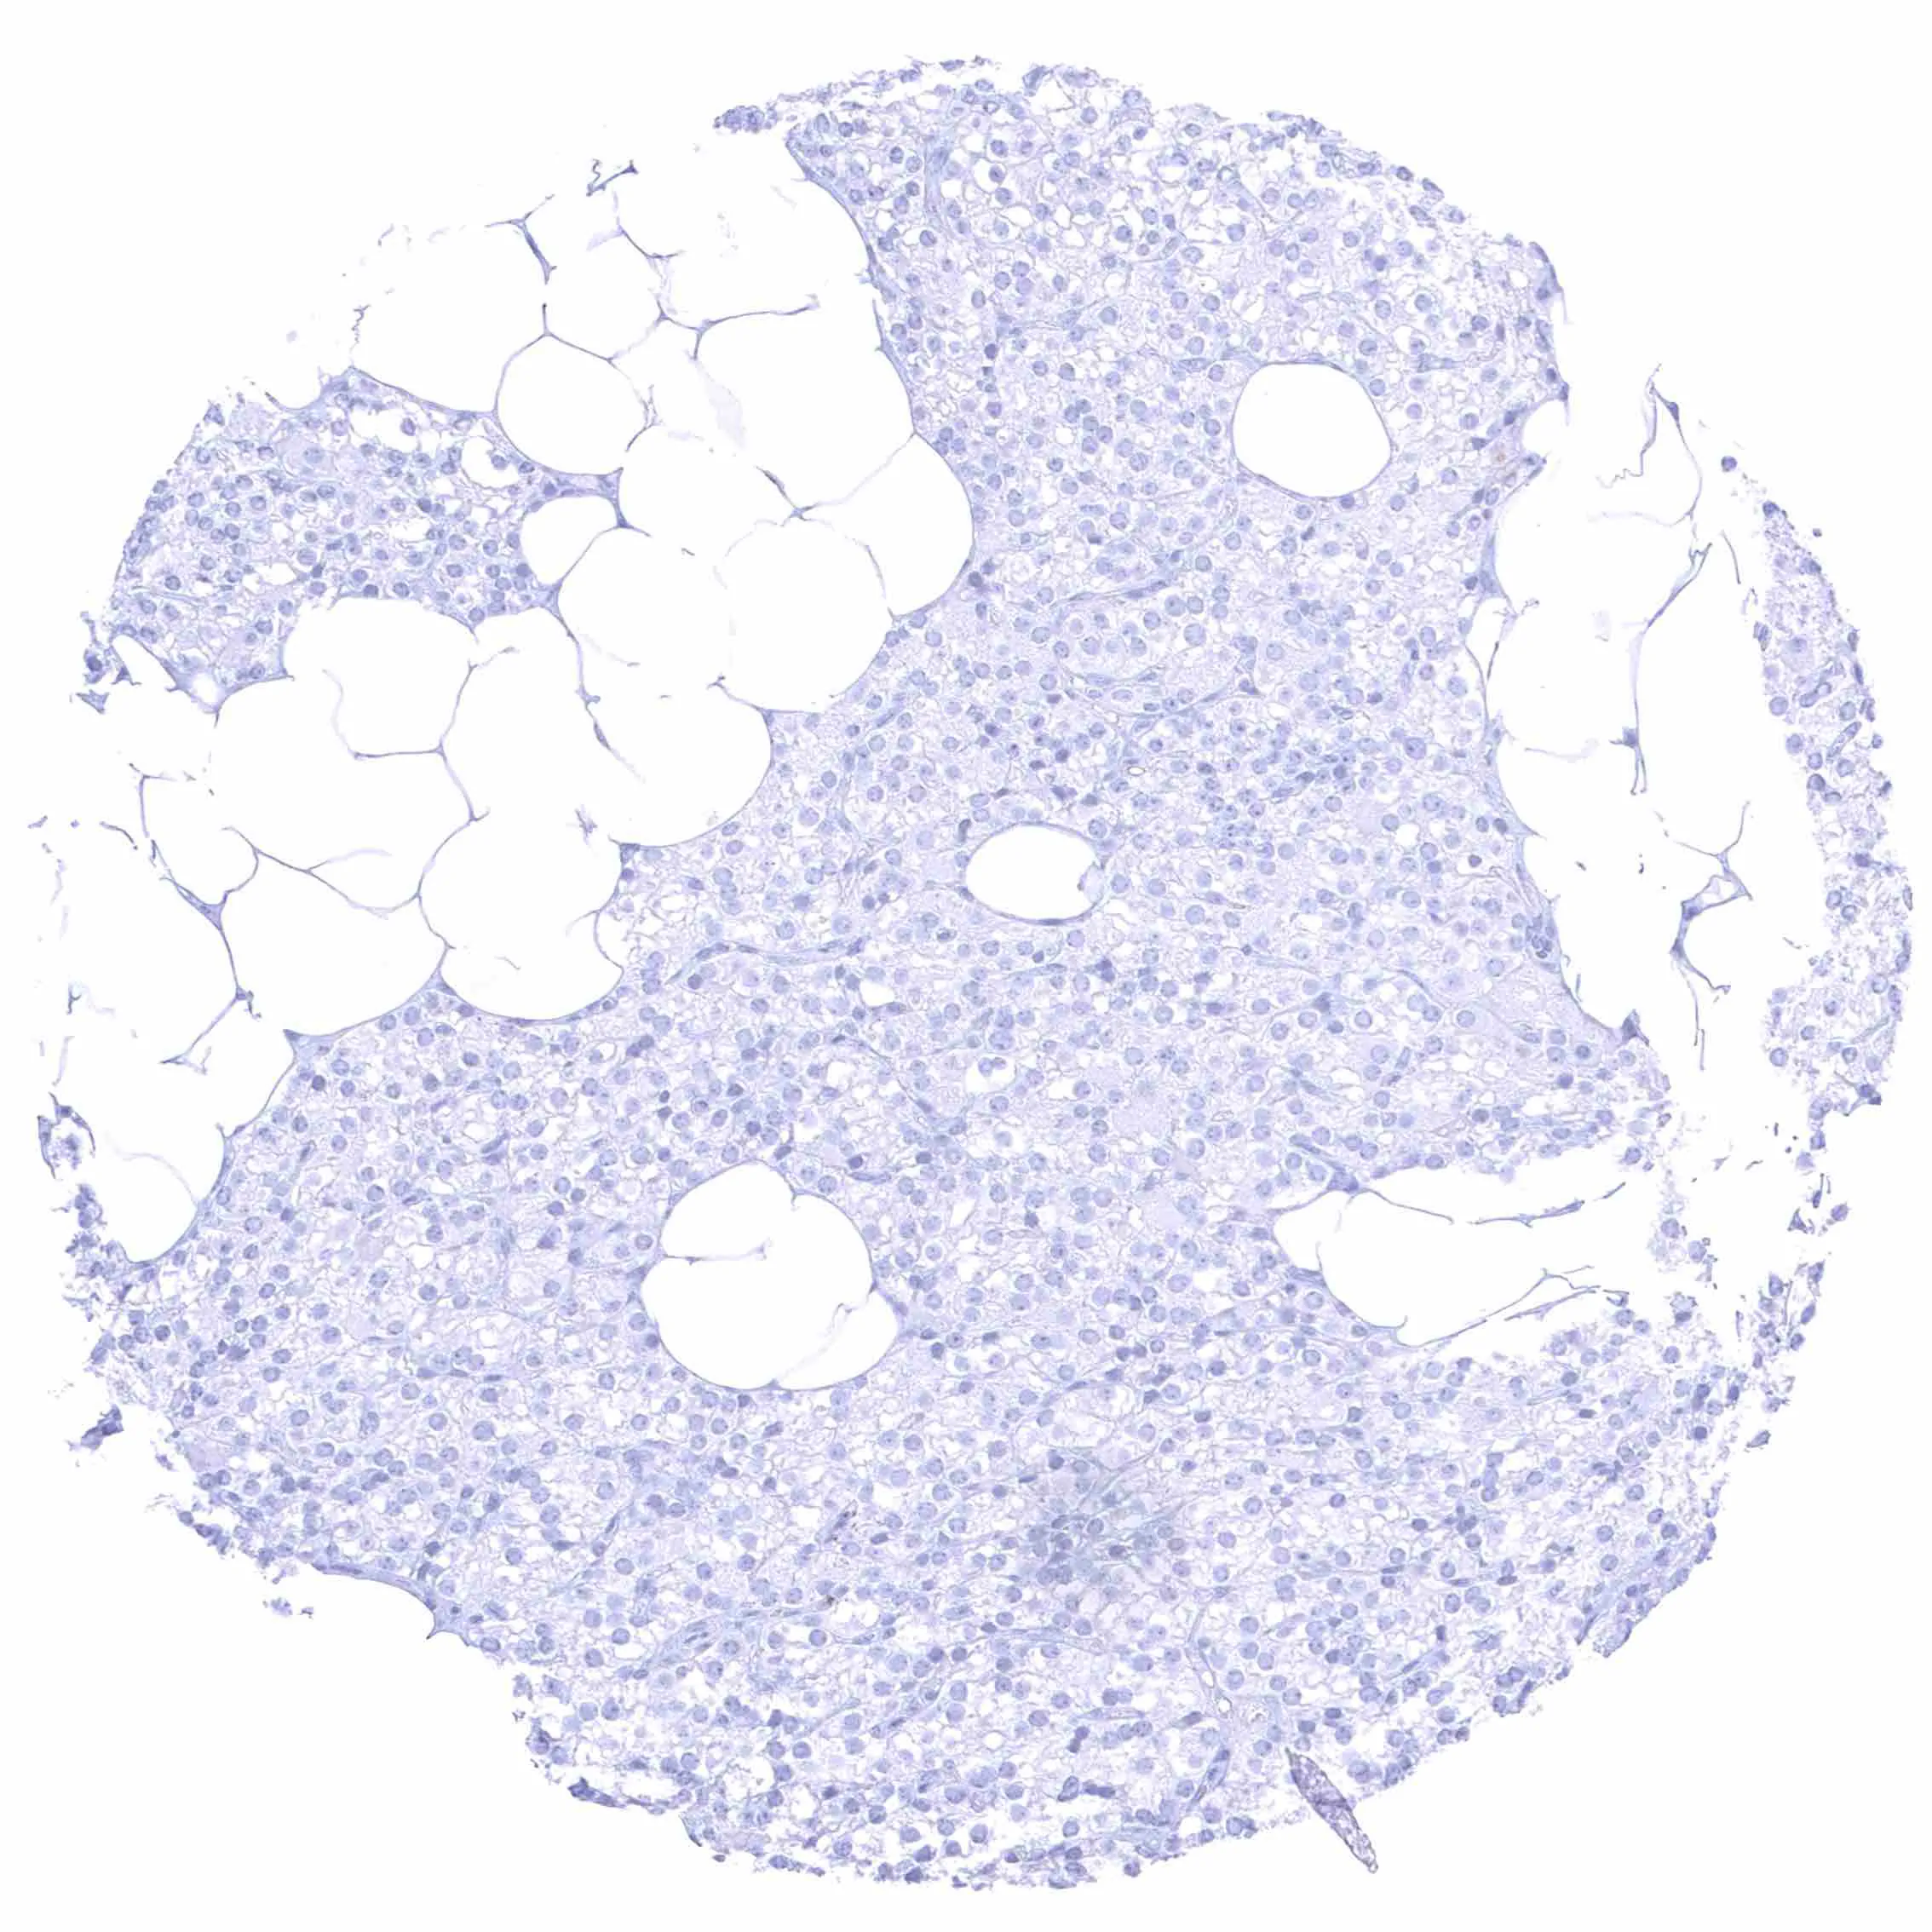

Lymph node